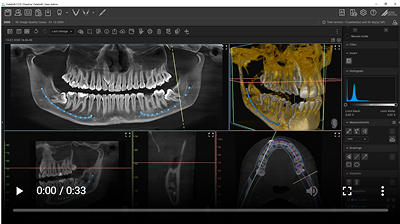

VistaSoft offers different views for the diagnosis of your CBCT images: pano views, transversal layer images (TSA) and multiplanar reconstruction (MPR). These can be rotated and tilted for perfect alignment. In the process, a "navigation head" always displays the current position so that orientation is much easier. The rendered OPG view provides you with even more assistance when navigating the 3D volume. The panorama curve required for this is automatically positioned by VistaSoft. Selection of the correct implant is facilitated by the easy process of drawing the nerve canal in the image.